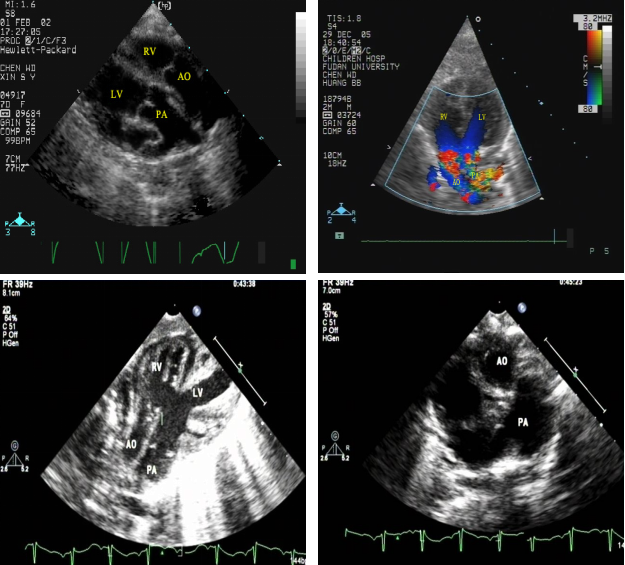

全性大动脉换位:超声心动图表现

完全性大动脉换位:心血管造影表现

◇ 右室压力与主动脉相等,肺动脉血氧饱和度高于主动脉

◇ 主动脉发自右室,肺动脉发自左室,主动脉空间位置异常并可显示是否合并冠状动脉畸形